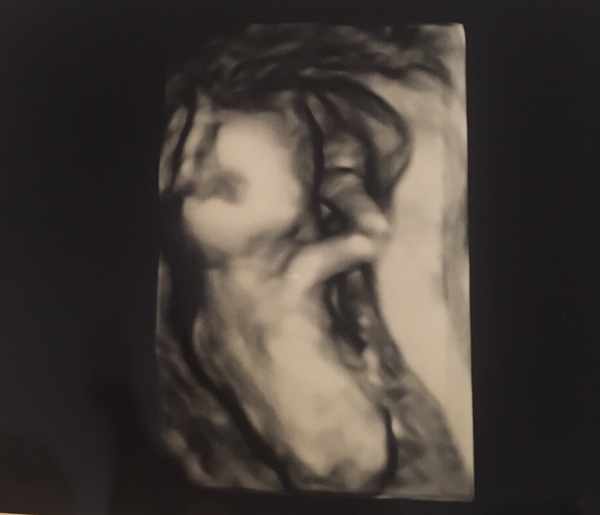

We caved and went for a gender scan at the weekend. We are having a boy! DH very happy and is already anticipating lego-related presents. The sonographer briefly switched to 3D but he was firmly keeping his back to us as the scan photo shows.

3D scan pic is still really good though!

Hazlulu, ahhh baby boy! How exciting!! Love the picture, even if it is of his back, it's amazing!!

Haz that scan pic is great!I am always amazed as to how well formed baby at this point.